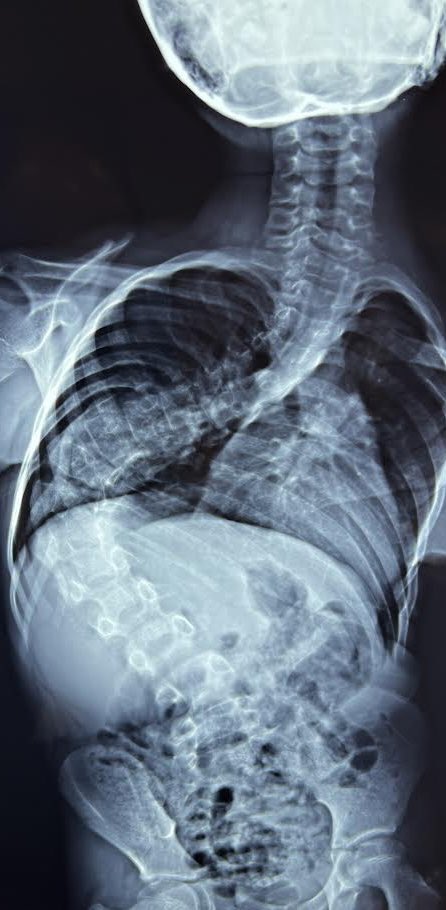

المهم ان ربنا اكرمنا اكتر مما كنا نتخيل و محمد بقي زي الفل و روحت دلوقتي بعد انتهاء الخمس عمليات اشوفه و اتمشي معي مرتين و اتصورنا و بعدين حطينا صورة قبل و بعد علي التلفونات جنب بعض انا و والد محمد…

و قعدنا نشوف الفرق و محمد بقي واحد تاني خالص غير بتاع الصبح